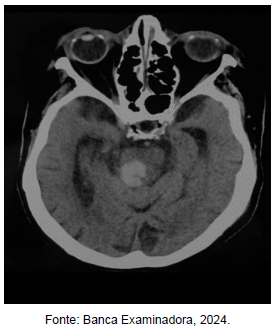

Com base na figura acima, em qual região do tronco cerebral está localizada a hemorragia?

Provas